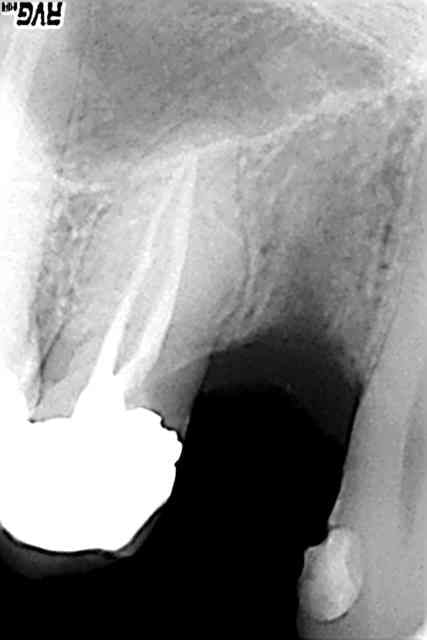

voici les radios avt aprés

R39 qex1zn - Eugenol

R36 afyhed - Eugenol